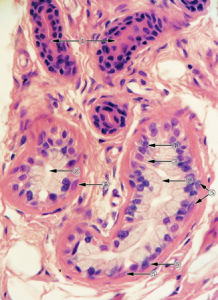

組織病理檢查,早期毛囊角栓並逐漸出現毛囊破裂,在頂泌汗腺及其擴張導管周圍有中性粒細胞浸潤,革蘭染色在腺體及真皮內有大量球菌,以及小汗腺亦受侵,在血管周圍有大量淋巴西部及漿細胞浸潤。最後腺體被破壞,腺體上皮碎片的四周有異物巨細胞浸潤。在癒合區域可見有廣泛纖維化,所有皮膚附屬檔案皆被破壞。